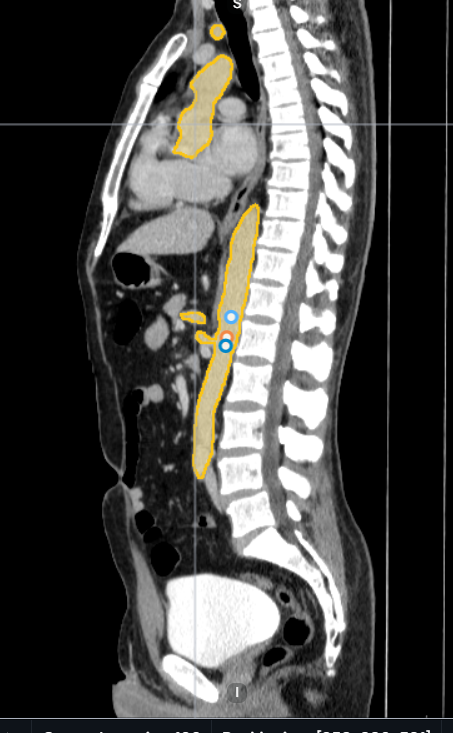

Medical image annotation is the process of labeling medical images, such as X-rays, MRIs, CT scans, and ultrasound images, to help AI models recognize patterns and abnormalities. This process involves trained radiologists, pathologists, and data annotators who precisely mark anatomical structures, tumors, and other critical elements within medical images.

1. Segmentation Annotation

- Identifies and labels different regions within a medical image, such as tumors, organs, and tissues.

- Used in oncology, cardiology, and neurology for precise diagnosis.

3. Polygon Annotation

- Creates detailed annotations for irregularly shaped structures in medical scans.

- Useful in dermatology, ophthalmology, and pathology for accurate disease detection.

5. 3D Image Annotation

- Used for volumetric scans like MRI and CT to analyze structures in three dimensions.

- Enhances AI capabilities in complex medical imaging.